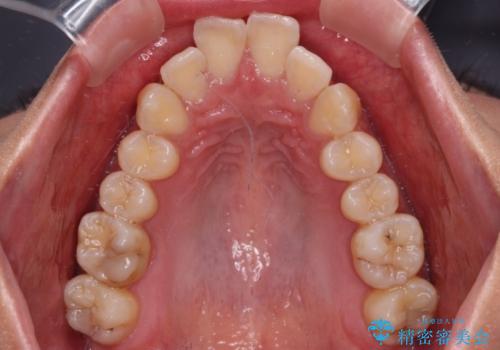

前に飛び出した上顎前歯をスッキリと引っ込める ワイヤー装置での矯正治療

- 上顎前歯の突出感を気にして来院された患者様です。

舌の突出癖の影響で、歯列が前方に飛び出いた形態となっている状態でした。

抜歯矯正とするような歯列ではないため、舌のトレーニングを行いながら歯列を側方に拡大させることで口元の突出感を改善することとしました。

横顔は元々突出した印象ではなかったのですが、上顎前歯の角度が改善したことで、唇の閉じにくさが改善されました。